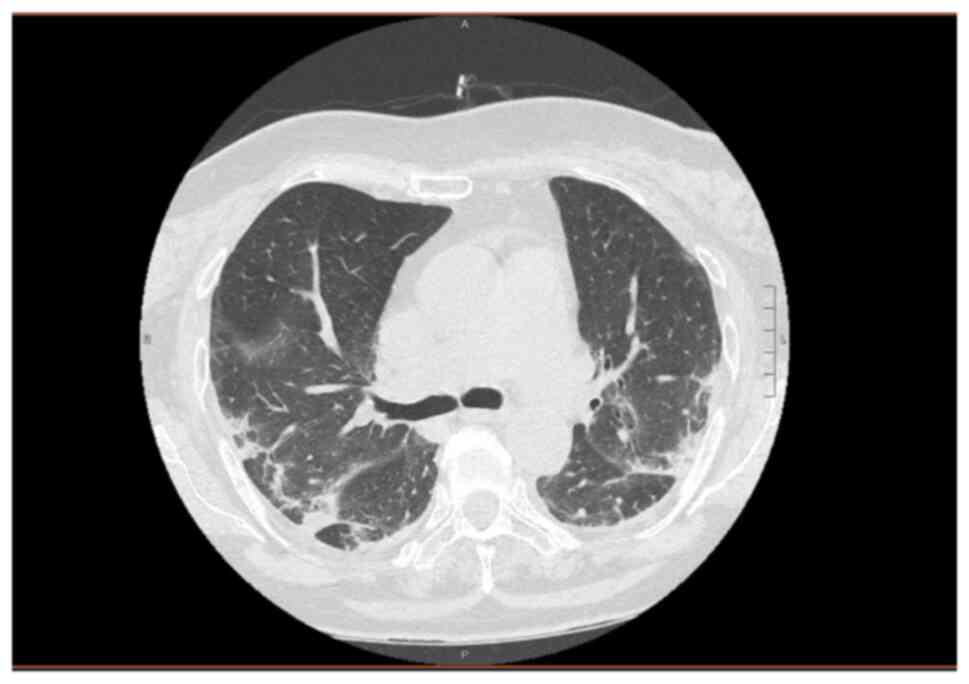

Sarilumab administration in patients with severe COVID‑19: A report of four cases and a literature review

Almost 2 years have passed since the World Health Organization declared a pandemic state for severe acute respiratory syndrome coronavirus 2 infection. The pathogenesis of coronavirus disease 2019 (COVID‑19) consists of an initial viral phase responsible for early symptoms followed by an inflammatory phase, which is cytokine‑mediated, responsible for late‑onset symptoms, culminating in acute respiratory distress syndrome. Considering that IL‑6 plays a key‑role in the development and maintenance of inflammation, drugs targeting both IL‑6 and IL‑6 receptors have been evaluated. The present study reports the cases of four hospitalized patients with severe respiratory COVID‑19 treated with a single dose of sarilumab, a monoclonal anti‑IL‑6 antibody, along with standard of care medications and oxygen therapy. A few days following sarilumab administration, the clinical and biochemical conditions began to improve, until the discontinuation of O2 therapy and discharge. The present study demonstrates that sarilumab may represent a promising drug that may be used to treat the hyperinflammatory phase; however, further trials are required to determine whether it should be used combination with other drugs or alone, and to better understand the pharmacokinetics and related side‑effects.

Figure 1

Figure 2

Figure 3

Figure 4